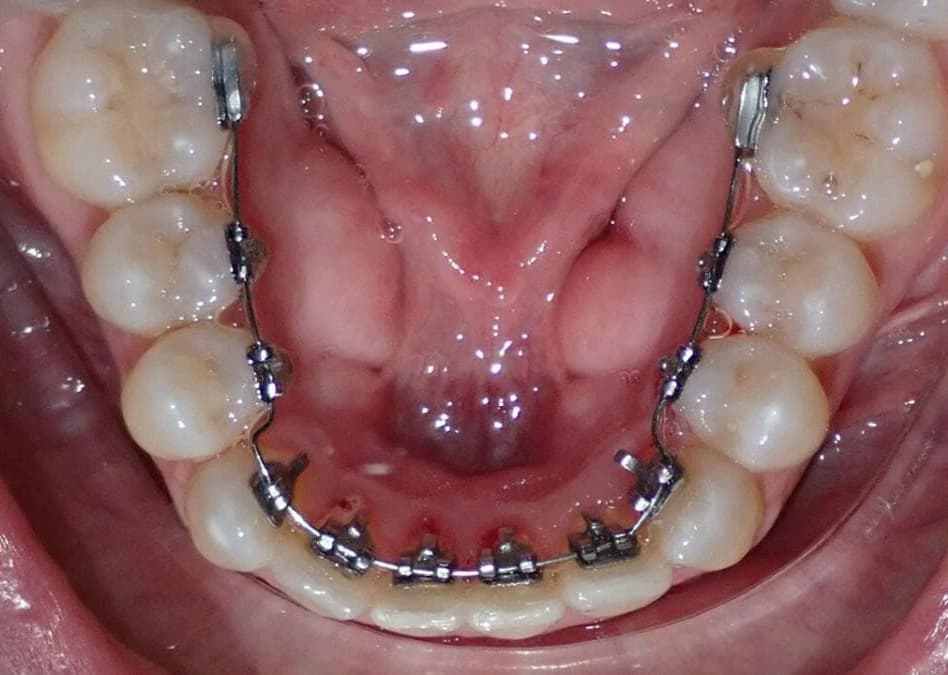

La Ortodoncia lingual es ideal para aquellos pacientes que desean que su tratamiento pase desapercibido. Este tratamiento es totalmente invisible, y son aparatos que van sobre la cara interna de los dientes.